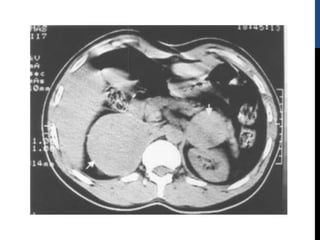

DIAGNÓSTICO

La localización del tumor debe realizarse después, y no

antes, de establecer el diagnóstico bioquímico de

feocromocitoma.

Las técnicas de imagen incluyen:

1. Tomografía computarizada

2. Resonancia magnética

3. Gammagrafía                                   con            metaiodobenzilguanidina                                              o        con

octreótido

TAC Y RMN

Por su tamaño (típicamente entre 2 y 5 cm) los

feocromocitomas son tumores fácilmente detectables tanto

por TC como por RM

La sensibilidad de la TC es superior al 93%

En la RM el feocromocitoma muestra característicamente

isointensidad respecto al hígado en T1 y es en cambio

hiperintenso respecto al hígado y a tumores suprarrenales

de otra estirpe en T2

La hipervascularización del tumor es evidente si se usa

gadolinio.